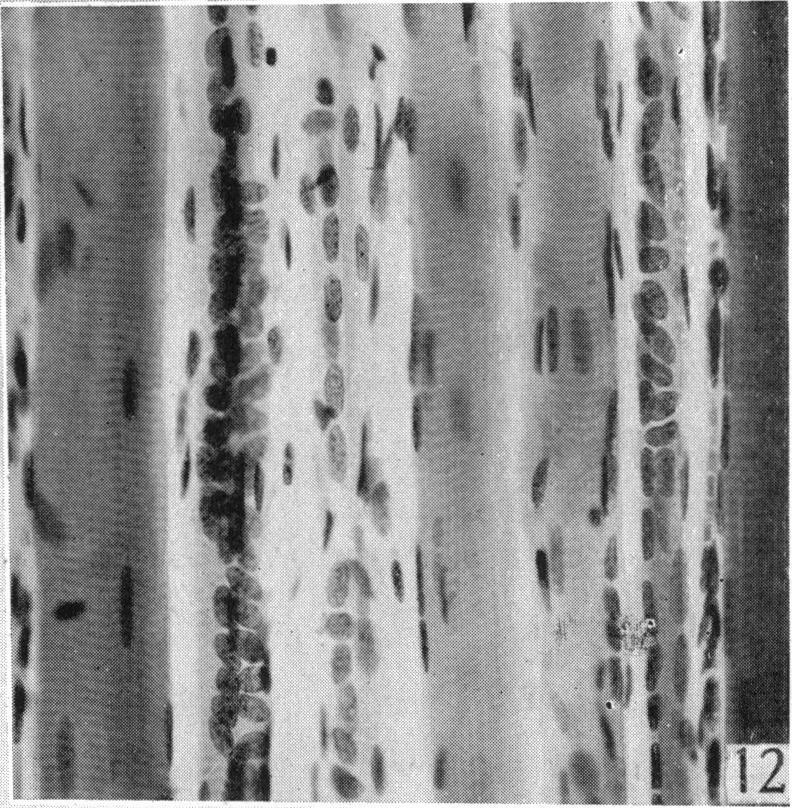

An experimental study of the regeneration of mammalian striped muscle.

J Anat. 1946 Jan;80(Pt 1):24-36.4.